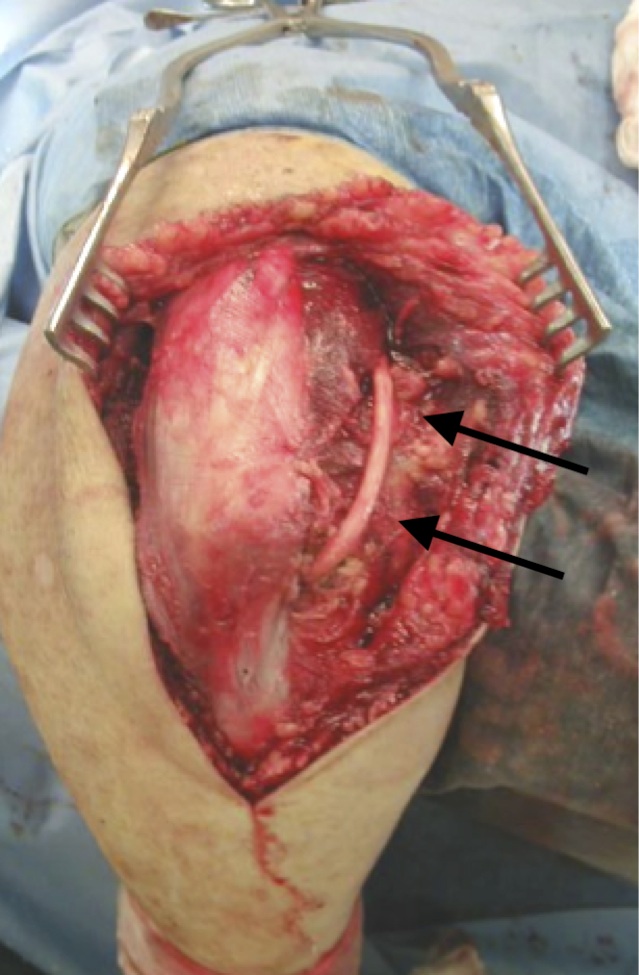

Triceps reflecting / Bryan Morrey

Technique

- release and protect ulna nerve

- mobilize medial border of the triceps including tendon from olecranon

- anconeus dissected off the ulna

- reflect triceps and anconeus from medial to lateral

- entire extensor mass is subluxated over lateral epicondyle

- leave